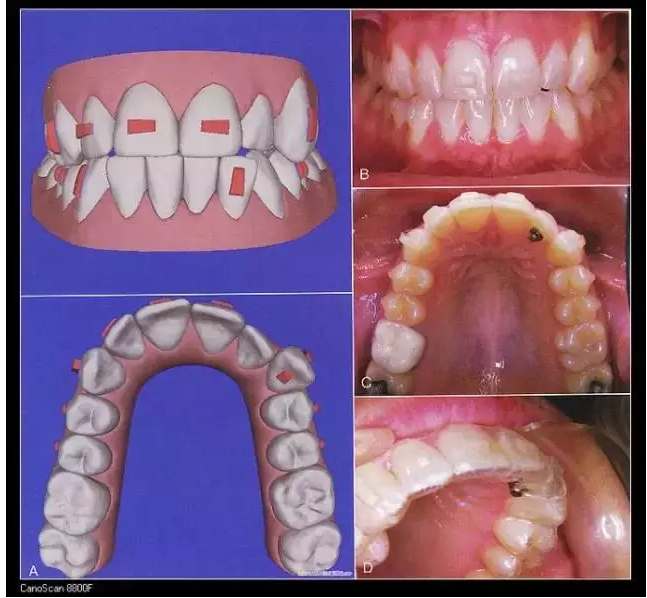

五、隱形矯治器

Invisalign隱形矯治器的原理是先在計(jì)算機(jī)里對醫(yī)生的印模進(jìn)行三維建模,按照正畸醫(yī)生的指導(dǎo)來設(shè)計(jì)挪動(dòng)牙齒,得到醫(yī)生的確認(rèn)后投入加工。每付矯治器少量移動(dòng)牙齒,兩周更換一副矯治器,在1-2年后完成牙齒的矯治。因?yàn)椴馁|(zhì)沒有金屬,受到很多白領(lǐng)的追捧,不過目前還不能夠治療所有的復(fù)雜病例。對付輕中度擁擠,輕度開合,牙縫散開等是不錯(cuò)的選擇。